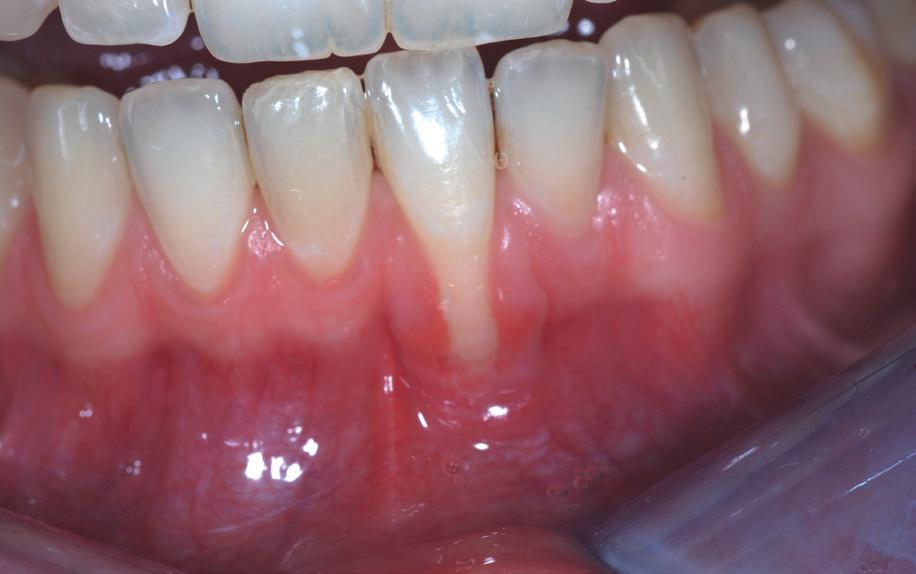

Na afronding van de eerste twee behandelstappen werd parodontale stabiliteit bereikt, zoals waarneembaar op de parodontiumstatus en (röntgen)foto’s (afbeelding 6, 8). De patiënt toonde aantoonbare verbetering in mondhygiëne (afbeelding 4) en bleef gemotiveerd om de behandeling voort te zetten.

4. Lichtfoto na infectie controle

De kwetsbaarheid van het onderfront

Vooral in het mandibulaire front, waar het bot van nature dun en smal is, zijn de risico’s het grootst.

Klinische observaties en literatuur (o.a. Teughels et al., 2009; Engelking & Zachrisson) tonen aan dat zodra de wortel van een element buiten het corticale bot wordt gebracht, het lichaam deze positie niet corrigeert met spontane botgroei. In plaats daarvan treedt botresorptie op, gevolgd door mucogingivale problemen. Patiënten die jaren na een orthodontische behandeling terugkomen met gingivarecessies, mobiliteit of wortelcariës blijken vaak onbewust slachtoffer van een (soms door retentie versterkte) standswijziging die torque-gerelateerd is. Met name bij een dun gingivaal biotype is de biologische tolerantie minimaal.

1. Onderfront pre-orthodontisch: zichtbare gingivarecessie bij de 31 ten gevolge schending van de biologische envelop.